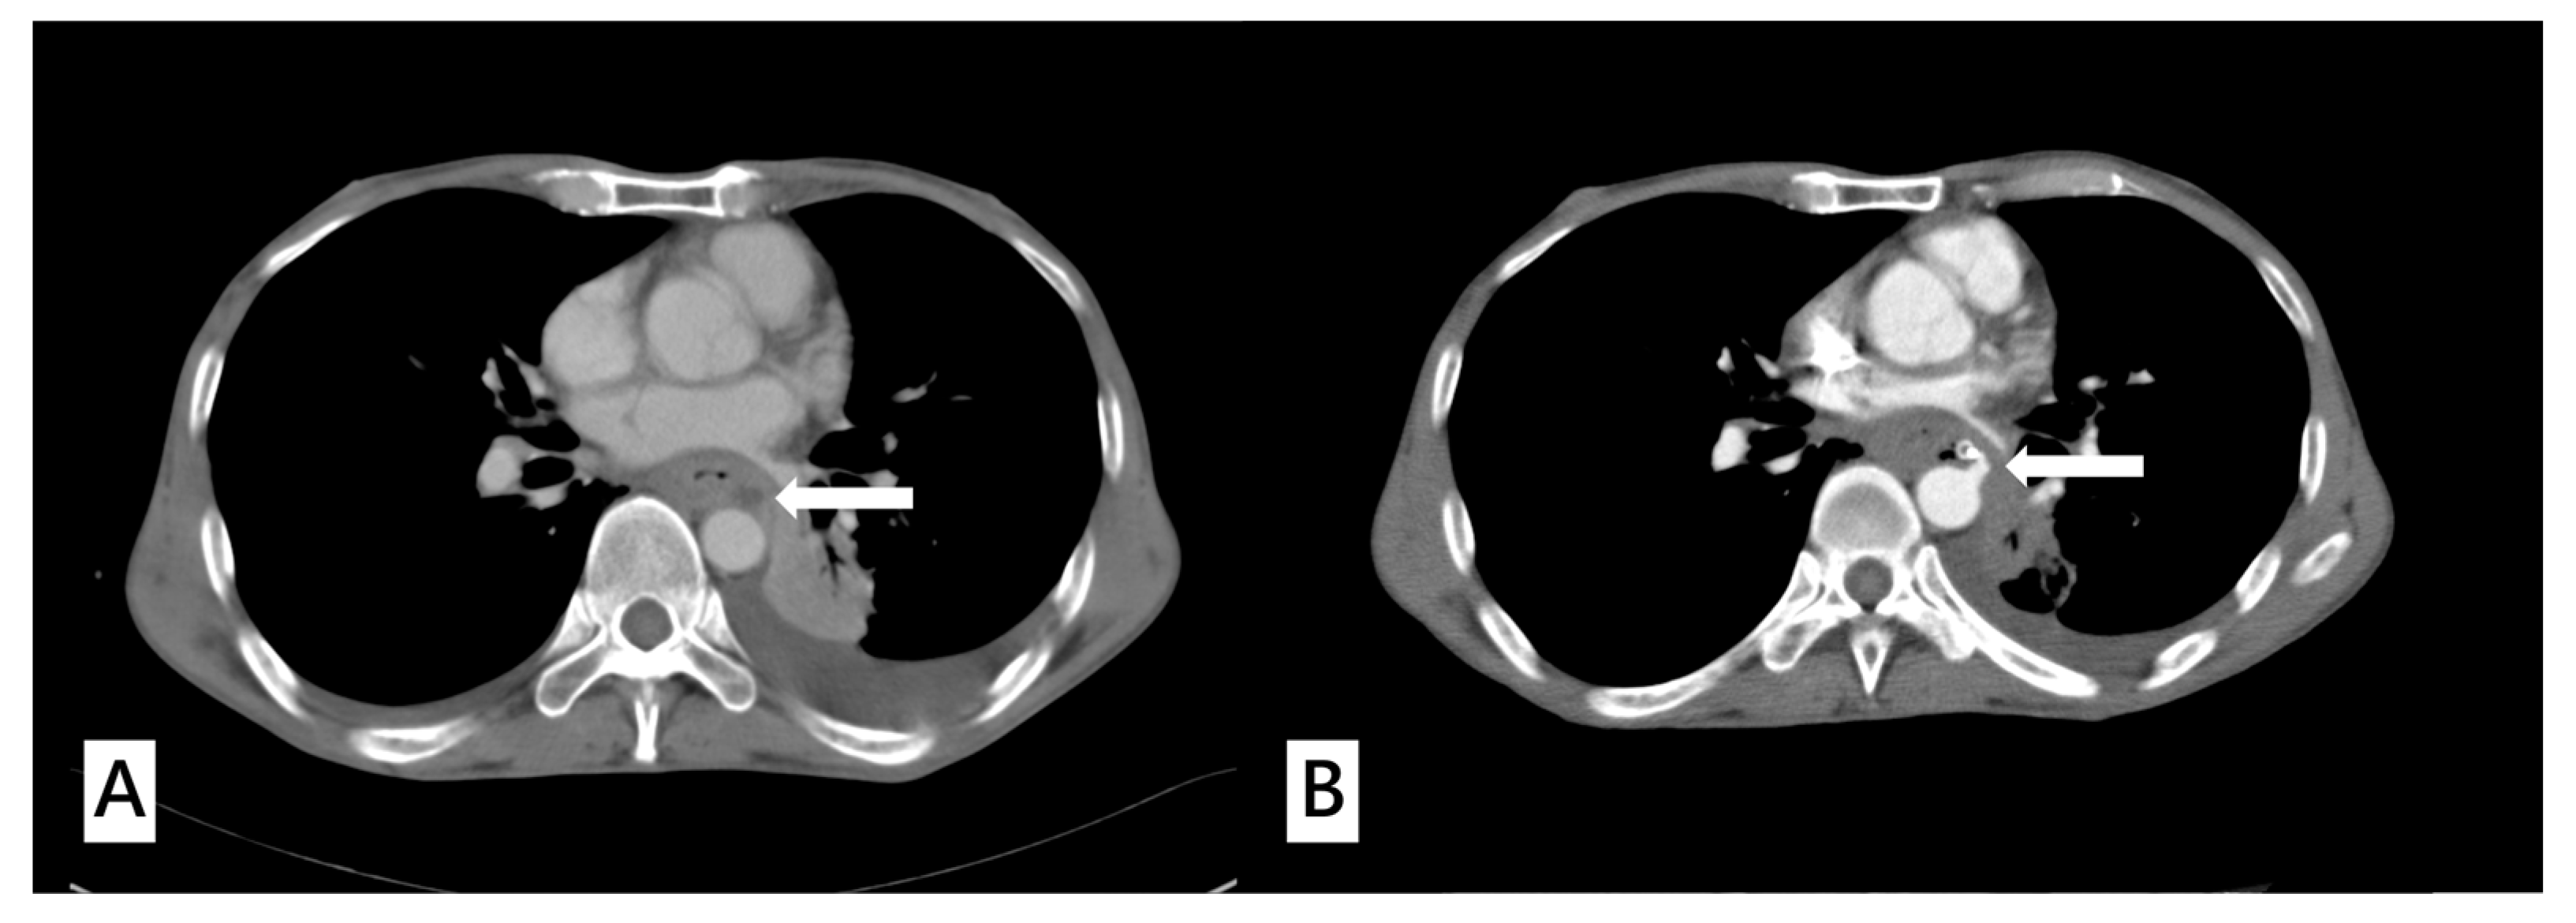

Figure 1.

(A) A 51-year-old male diagnosed with upper gastrointestinal bleeding caused by advanced thoracic esophageal cancer. The computed tomography angiography (CTA) of aorta revealed a tumor ulcer abutting the aorta with esophageal obstruction (white arrow). (B) The same patient presented with hematemesis and was sent to the emergency department 30 days later. Repeated CTA of aorta showed extravasation from the aortic arch abutting the esophagus (white arrow) with a high suspicion of aorto–esophageal fistula.